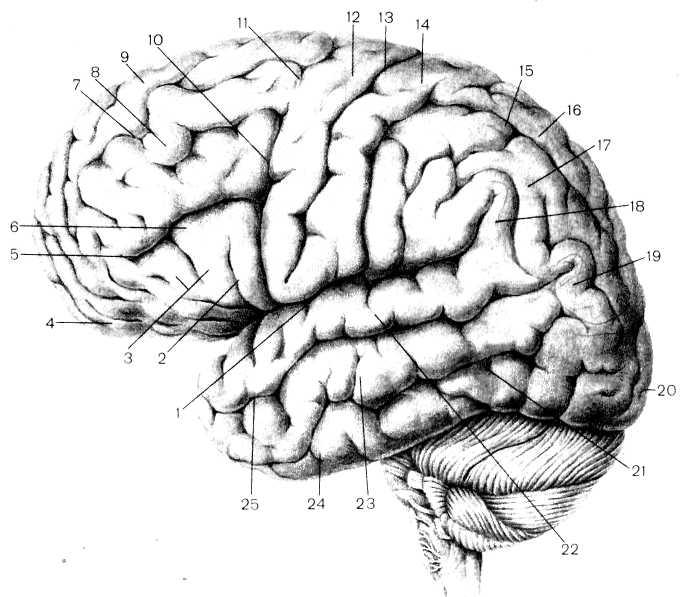

Анатомические снимки верхнелатеральной поверхности головного мозга